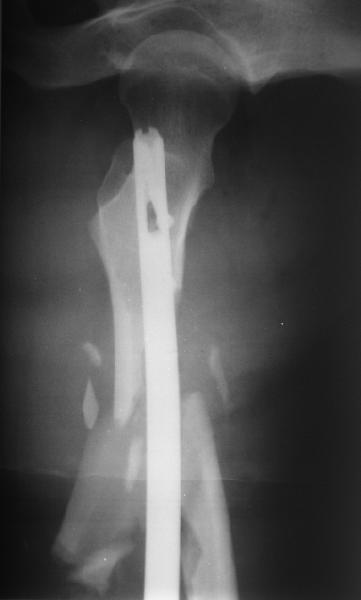

Мы бы не стали открывать, такие переломы срастаются, хотя бы и с краевым дефектом. То есть если удалять стержень потом, то сильно попозже обычного. В приложении пример. Сразу после операции и через 11 мес. Понятное дело, пациент к тому времени давно и не хромал, и функция колена была полная.

Уважаемые коллеги! От имени Алексея Смирнова всем спасибо за обсуждение. Больной прооперирован. Снимки в приложении.